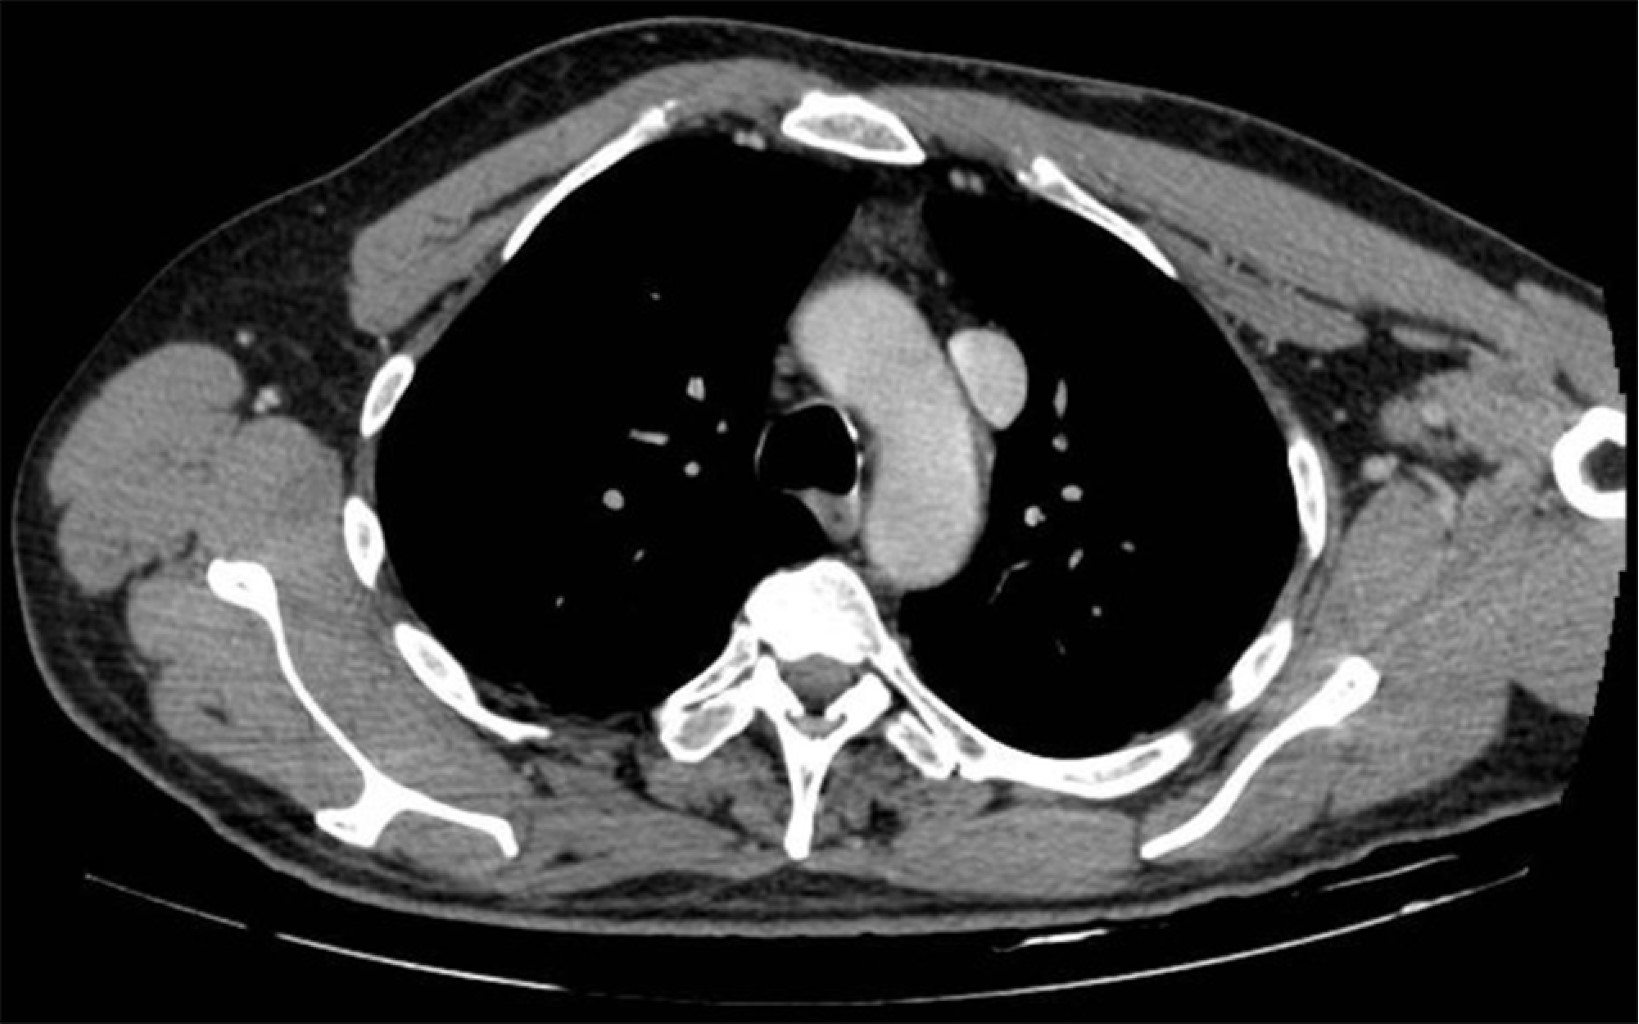

Malposition of central venous catheters is associated with important and underestimated risks. Although some factors have been related with malposition, its cause is generally not diagnosed, and it seems to have multifactorial origin. We present two cases of central venous catheter malposition due to unusual anatomical causes, diagnosed in the perioperative period. In the first case, superior vena cava agenesis was diagnosed during mitral replacement by sternotomy, which was logically associated with malposition of the inserted central line. The use of catheters and devices through jugular and subclavian veins in patients with this infrequent pathology is associated with important limitations and serious potential complications. In the second case, an undiagnosed goiter causes bilateral and simultaneous malpositioning of two inserted central venous catheters, in the context of an emergency situation, in both internal jugular veins.

Figure 4